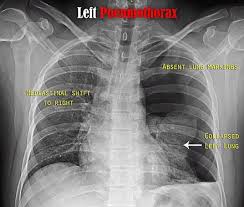

In this video, you'll learn how to identify when radiological pleura is abnormal and the key signs to look out for when trying to diagnose a pneumothorax. Check spelling or type a new query. When pneumothorax with its accompanying emphysema occurs as a complication of bronchoscopy, symptoms are usually severe, and require treatment. When a pneumothorax is clinically suspected, we routinely perform cxr on both inspiration (as per usual) and expiration. Agus suharto basuki, sp.p fakultas kedokteranuniversitas muhammadiyah surakarta 2011 2. Scarcely less important is the selection of the positionmost favorable for obtaining information in fluoroscopicand Special attention is paid to tension pneumothorax, to. A pneumothorax, légmell (ptx), az az életveszélyes akut kórállapot, amikor a mellhártya zsigeri és fali lemeze közé, azaz a mellhártyaüregbe levegő jut kívülről (a mellkasfal sérülésén át) vagy belülről (a tüdő vagy oesophagus folytonosságmegszakadása útján).

In this video, you'll learn how to identify when radiological pleura is abnormal and the key signs to look out for when trying to diagnose a pneumothorax. Ennek következtében súlyos respiratoricus állapotromlás következhet be, amely mielőbbi orvosi. Therefore, it is mandatory to treat it safely. Primärer spontanpneumothorax, es besteht keine gesicherte ursache und die betroffene person ist gesund. Tillståndet uppstår ofta spontant hos unga och friska utan känd lungsjukdom, men kan drabba alla åldrar med eller utan tydlig orsak Louis duringthepast fewyears, therehave been many importantadvances in the diagnostic method of thoracic conditions. We did not find results for: Patients with tension pneumothorax usually appear dyspnic and distressed. All 28 control roentgenograms were scored correctly. Cannot be detected even by the roentgen rays. Sekundärer spontanpneumothorax, wird durch lungenerkrankungen oder krankheiten anderer organe verursacht. Primær spontan pneumothorax (psp) opstår primært hos yngre (ofte under 45 år), lungeraske personer, og antages at skyldes bristning af subpleurale blærer/blebs. It entails few complications and little risk.

Pneumo, luft, och thorax, bröstkorg) är ett tillstånd då ena eller båda lungorna komprimeras till följd av luftansamling i lungsäcken. Hence, if one considered selective pneumothorax as a sign of pathology in. Temaet er også relevant for andre helsefagutdanninger. Chest (1977), 71, 211 bilateral spontaneous pneumothorax with pulmonary metastases from synovial cell sarcoma harjit singh, nachhattar singh and ravinderpal kaur government medical college and rajindra hospital, patiala, punjab, india summary the association of bilateral spontaneous pneumothorax with pulmonary metastases is rare. Røntgen af thorax viser en luftlomme med en synlig visceral pleuralinie (konveks mod brystvæggen), nogle gange foreligger der også lidt pleuravæske 1 ved en mindre pneumothorax (kappepneumothorax) er afstanden fra pleura viscerale (lungekanten) til indersiden af brystvæggen mindre end 2 cm thoraxrøntgen med forskellige typer af pneumothorax Cannot be detected even by the roentgen rays. It occurs through an immediate disruption of the visceral pleura that results in an accumulation of air in the pleural space. Ennek következtében súlyos respiratoricus állapotromlás következhet be, amely mielőbbi orvosi. Distinctive variability in forms of effusions and to special methods. Maybe you would like to learn more about one of these? It entails few complications and little risk. Sekundärer spontanpneumothorax, wird durch lungenerkrankungen oder krankheiten anderer organe verursacht. When a pneumothorax is clinically suspected, we routinely perform cxr on both inspiration (as per usual) and expiration.

Røntgen af thorax viser en luftlomme med en synlig visceral pleuralinie (konveks mod brystvæggen), nogle gange foreligger der også lidt pleuravæske 1 ved en mindre pneumothorax (kappepneumothorax) er afstanden fra pleura viscerale (lungekanten) til indersiden af brystvæggen mindre end 2 cm thoraxrøntgen med forskellige typer af pneumothorax pneumothorax. Røntgen af thorax viser en luftlomme med en synlig visceral pleuralinie (konveks mod brystvæggen), nogle gange foreligger der også lidt pleuravæske 1 ved en mindre pneumothorax (kappepneumothorax) er afstanden fra pleura viscerale (lungekanten) til indersiden af brystvæggen mindre end 2 cm thoraxrøntgen med forskellige typer af pneumothorax